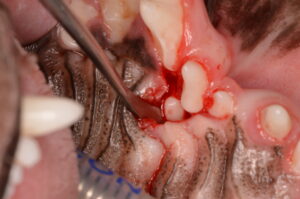

埋伏していた歯は、慎重に骨を削りながらアプローチし、残根を残さず完全に摘出することができました。

併せて、

- 全体的なスケーリング(歯石除去)

- ポリッシング(歯面研磨)

を行いました。